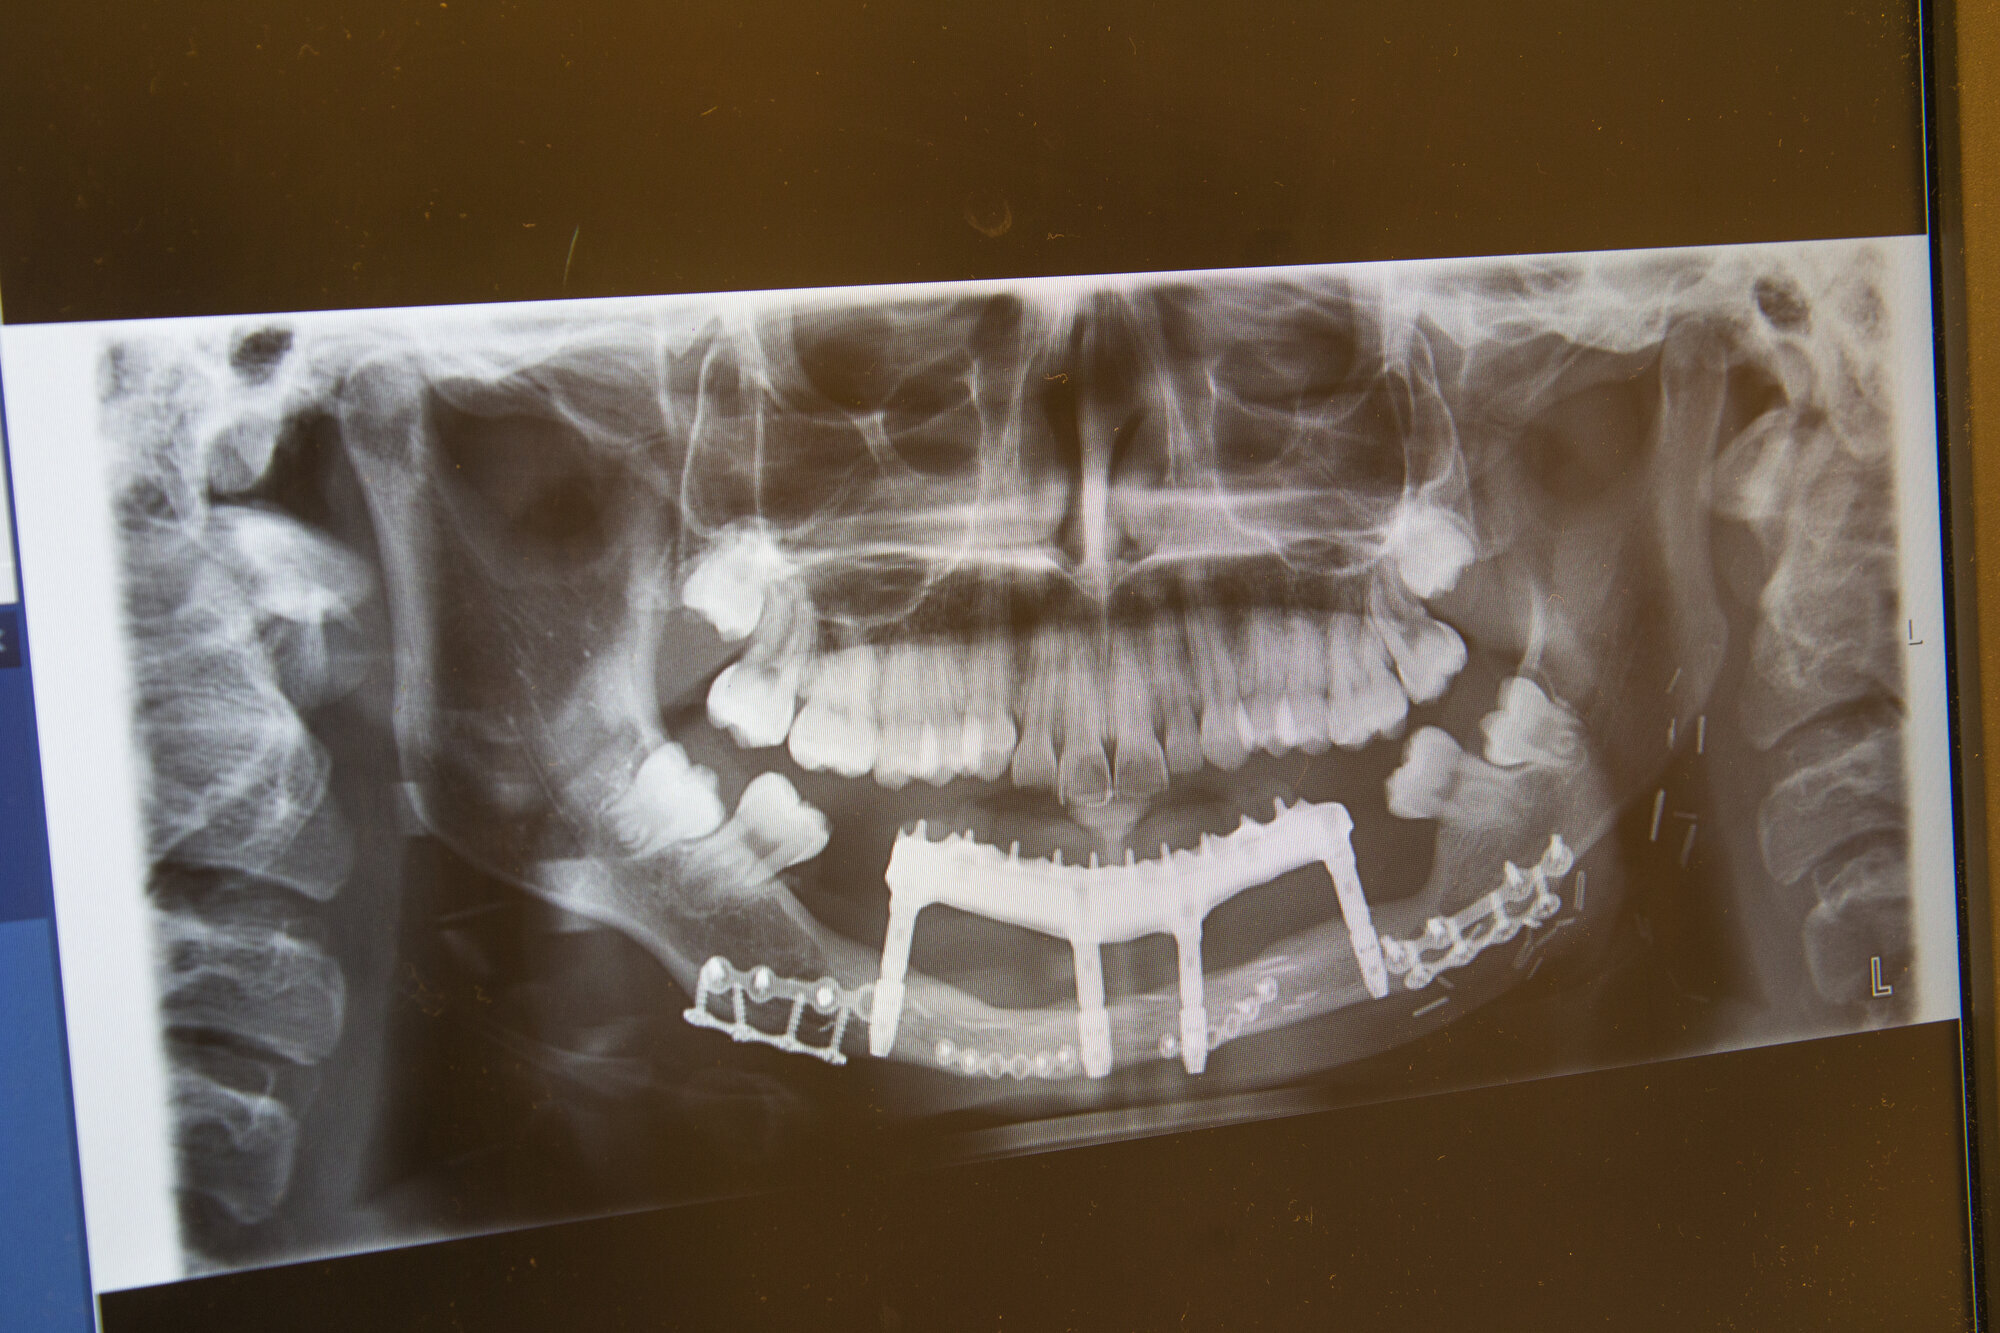

I sjeldne tilfeller rammes barn av beinkreft. På pc-en viser Berstad et røntgenbilde av en tolv år gammel pasient som fikk osteosarkom i underkjeven.

– Tolvåringen, som etter hvert skulle begynne på ungdomsskolen, kunne ikke gå rundt tannløs. Da er det fint å være del av et høyspesialisert sykehus med mange dedikerte spesialister. Alle sto på for å hjelpe. Tumoren og hele kjeven med tenner ble fjernet. Kjeven ble erstattet av en del av leggbeinet (fibula).

I en tolvtimersoperasjon ble både kreften fjernet og ny kjeve rekonstruert. Et svært team var involvert.

Berstad var med på å forme den ny kjeven av leggbeinet. I en senere operasjon satte hun inn fire implantater som ble skrudd ned i kjeven. Hver skrue er en slags kunstig tannrot. Når dette har grodd, skrus tennene fast i implantatene.